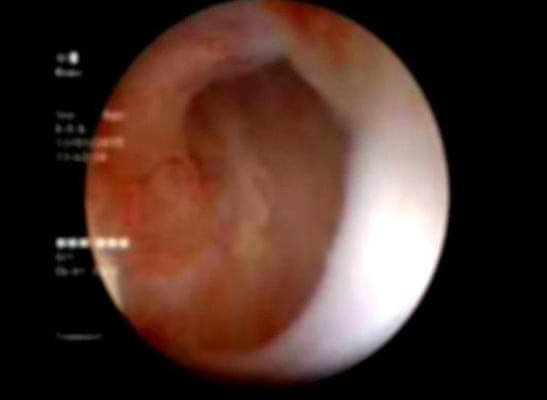

Figure 2: Follow-up Urethroscopy view at the implantation site: pink granulating tissue covering the urethrotomy site.

After urethral catheter removal, all patients voided well with a good stream. There was a symptomatic improvement in all patients, and uroflow improved with a mean flow of 24 mL/s. The check Urethroscopy carried out at 6 months, 1 year and after 2 years are shown in Fig 2,3,4. Four patients were voiding well and did not require any auxiliary procedure at 3 years of follow up. Recurrence was seen in two patients at 18 months in one patient and at 2 years in the other.